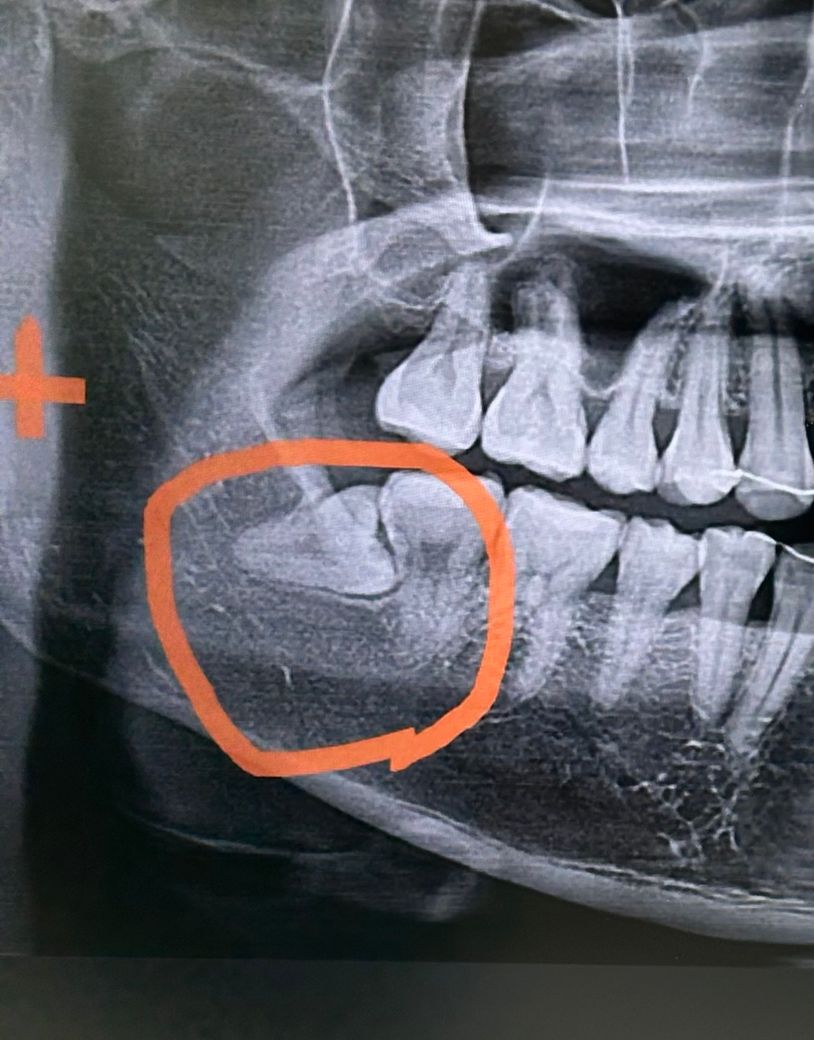

매복사랑니 발치 후 광대까지 통증이 있어요

6일전 매복사랑니 발치를 했습니다

약먹는 4일 동안은 안아팠는데 약 복용이 끝난 후 부터는 발치부위부터 광대뼈 아래까지 욱신거린 느낌이 계속 지속 됩니다 (통증는 10에서 5정도 입니다)

특히 음식을 먹으면 발치부위가 좀더 아픕니다

혹시 인비절라인 교정을 하면서 더 아픈건지, 혹은 드라이소켓? 증상인지 궁금합니다

사랑니 발치를 하면서 입을 오래 벌리고 잇어서 그럴수도 있습니다. 드라이 소켓은 아닌거 같으니 시간이 지나면 괜찮아 지실꺼에요.

보통 드라이소켓이라면 악취가 동반됩니다 통증이 아직 있다면 상비약 진통제를 좀 더 드시기 바랍니다